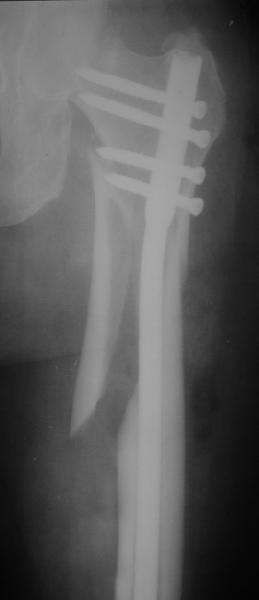

Это было года 2,5 назад, мы тогда еще уточняли возможности шинирования с угловой стабильностью гвоздем с поперечным расположением винтов при переломах проксимального отдела бедра. Пациенту не пришлось приобретать намного более дорогой рекон или проксимальный гвоздь. В приложении еще несколько примеров применения того гвоздя при высоких переломах бедра, в том числе с более латеральной точкой входа. Гвоздь изгибаем для этого.

Конечно, мы не синтезируем остеопорозые вертельные переломы согласно прилагаемому примеру, винты 6 мм вырежутся. Но у более молодых при хорошем качестве кости такие или подобные гвозди с поперечным расположением винтов вполне применимы для меж- и подвертельных переломов.

Картинка красивая, но на мой взгляд, не совсем оптимальная: Слишком медиально введён стержень - риск аваскулярного некроза головки бедра.

расположении сопредельных отломков- хорошая локальная васкуляризация. В приведённом случае я бы предпочёл принцип межфрагментарной компрессии (рекон/гамма нэйл 130- 135) принципу шинирования перелома.

Поясни, пожалуйста, почему решил шинировать косой чрезвертельный перелом?